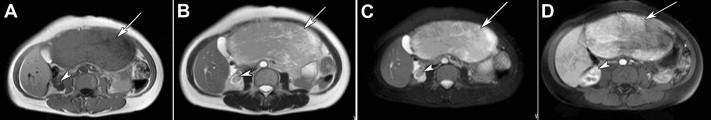

All patients received ultrasonography and computed tomography (CT) examinations, but only two patients received magnetic resonance imaging (MRI). On sonography, the tumors were seen as a hyperechoic mass, either homogeneous or heterogeneous. The lesions exhibited well-demarcated mass with heterogeneous density in plain CT scan. In arterial CT, the lesions were heterogeneously enhanced. In the portal venous phase, the lesions returned to an isoattenuating state (Fig. 1). In a 37-year-old woman complicated with renal PEComa, MRI showed heterogeneous hypointensity on T1-weighted images (T1WIs) and hyperintensity on T2-weigthed images (T2WI). After fat saturation, hyperintensity on T2WI in the liver lesion remained, but T2WI in the renal lesion showed hypointensity. In enhanced scanning, the lesions showed asymmetrical enhancement in arterial phase images (Fig. 2). In a 52-year-old woman with multiple liver lesions, MRI showed a lesion located on the left lobe and S8 of the liver. The lesions showed heterogeneous hypointensity on T1WI and heterogeneous hyperintensity on T2WI. After fat saturation, hyperintensity on T2WI remained. In enhanced scanning, the lesions showed asymmetrical enhancement in arterial phase images (Fig. 3). Prior to operation, one case was diagnosed with hepatic PEComa, three cases with hepatocellular carcinoma, and one case with hepatic adenomata.

MR image of multiple hepatic perivascular epithelioid cell tumors in a ...

Figure 3.

MR image of multiple hepatic perivascular epithelioid cell tumors in a 52-year-old woman. (A) T1-weighted MR image showed a heterogeneous hypointense mass in the left lobe (arrows). (B) T2-weighted MR image showed the same lesions in the left lobe with heterogeneous hyperintensity. (C) T2-weighted fat-suppressed MR image showed heterogeneous hyperintensity in the liver lesion in the left lobe. (D) During the hepatic arterial phase, the lesions in the left lobe showed asymmetrical enhancement. (E) T1-weighted MR image showed a heterogeneous hypointense mass in S8 (arrowheads). (F) T2-weighted MR image showed the same lesions in S8 with heterogeneous hyperintensity. (G) T2-weighted fat-suppressed MR image showed heterogeneous hyperintensity in the liver lesion in S8. (H) During the hepatic arterial phase, the lesions in S8 showed asymmetrical enhancement. MR = magnetic resonance.